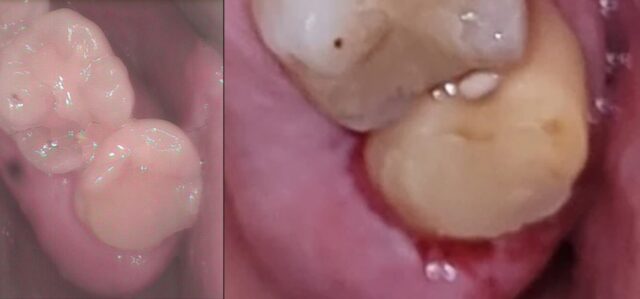

歯ぎしりの方の奥歯 銀歯交換 金属から白い歯に e.maxインレー イーマックス

emax e.max イーマックスインレー セラミックインレー 2023